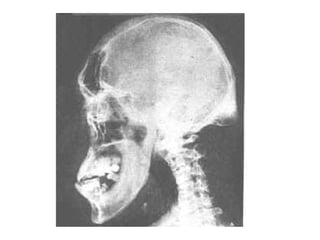

Acromegaly

• Acromegaly is a serious condition that occurs

when the body produces too much of the

hormones that control growth. ・ The hormone

most often affected is called growth hormone, or

GH. It ハ is produced by the pituitary gland, a tiny

organ at the base of the brain. ・・ Growth

hormone ハ promotes growth of bone, cartilage,

muscle, organs, and other tissues. ・・ When

there is too much growth hormone in the body,

these tissues grow larger than normal. This

excessive growth can cause serious disease and

even premature death.